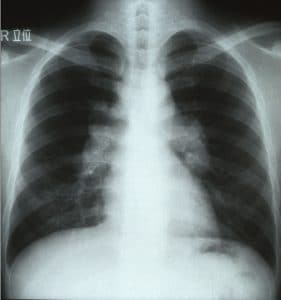

结节病最常见地影响肺部:约90%的结节病患者具有肺形式的疾病。主要症状是持续的咳嗽和呼吸急促。结节病也会影响皮肤,在那里它会导致嫩红色凸块和皮疹出现。然而,虽然这些是条件最常见的类型,但顺序化也会影响其他器官。如果发生这种情况,症状可包括红色,痛苦的眼睛,关节或肌肉疼痛,疲劳和嗜睡和腺体 - 等等。这种广泛的症状,没有一个特异性对齐,使其成为难以诊断的困难。用于诊断条件的测试取决于哪些器官似乎受到影响。例如,胸部X射线可以有助于诊断肺结气。